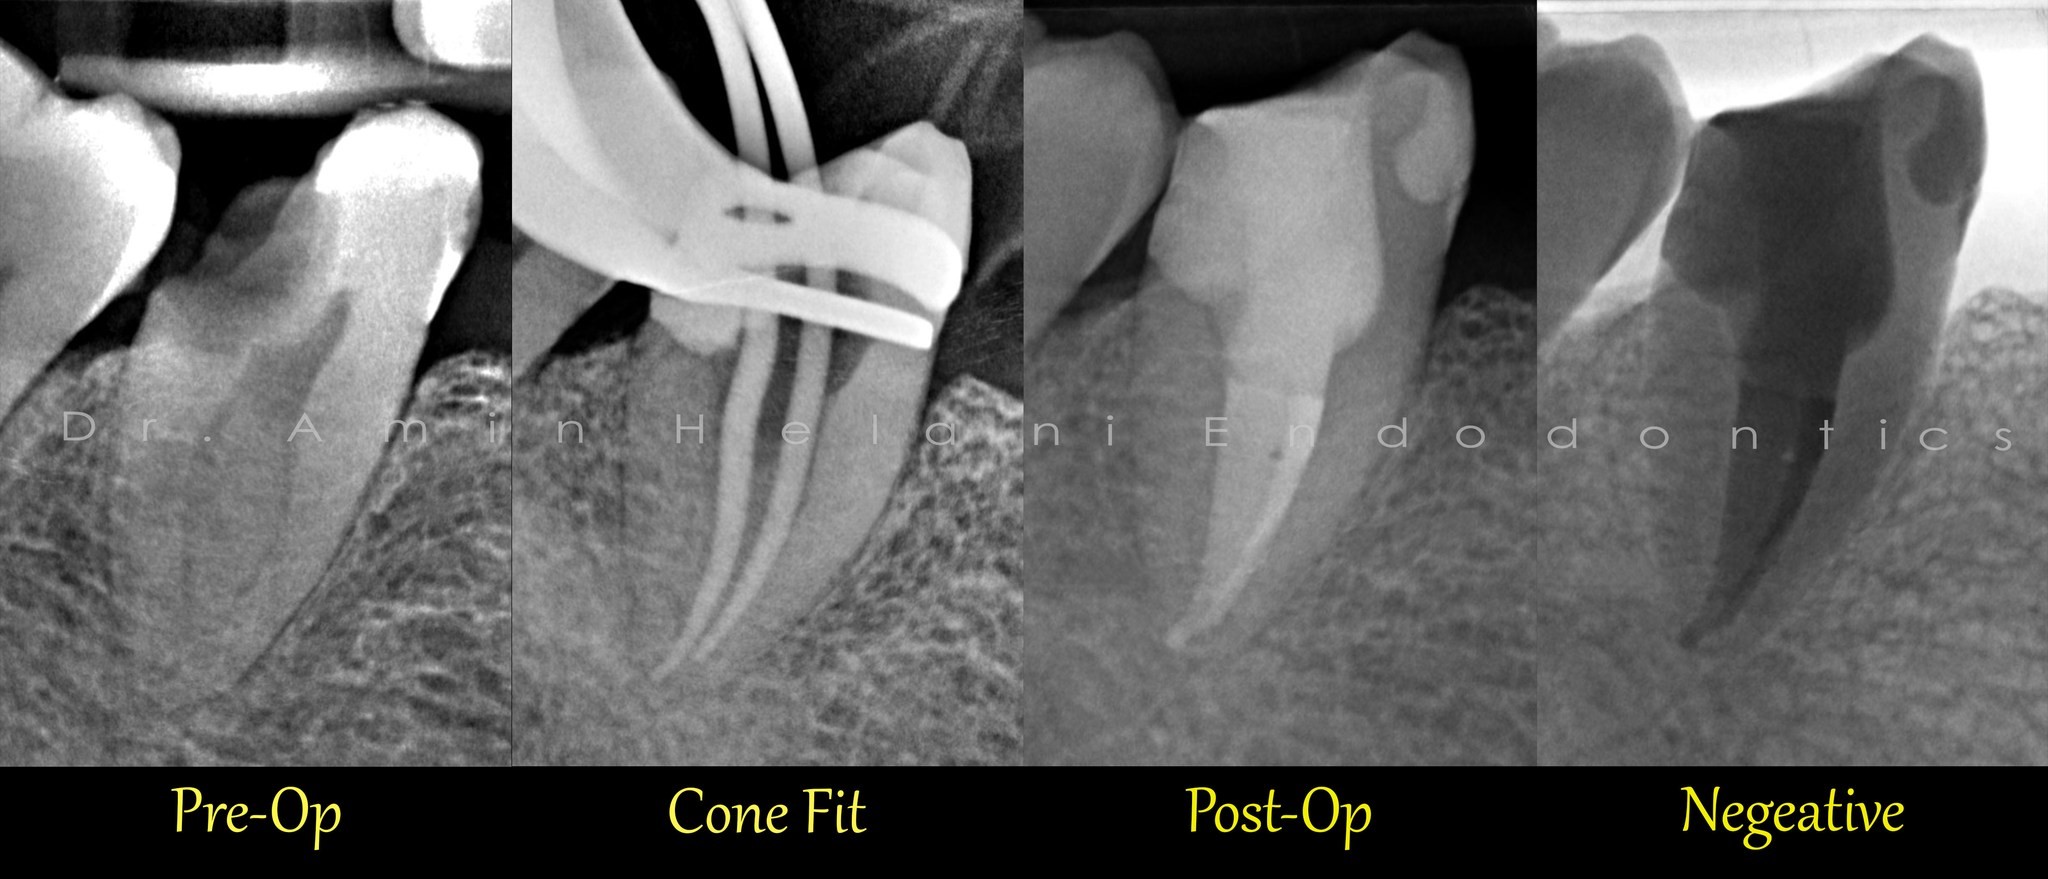

Perforation schließen mit MTA